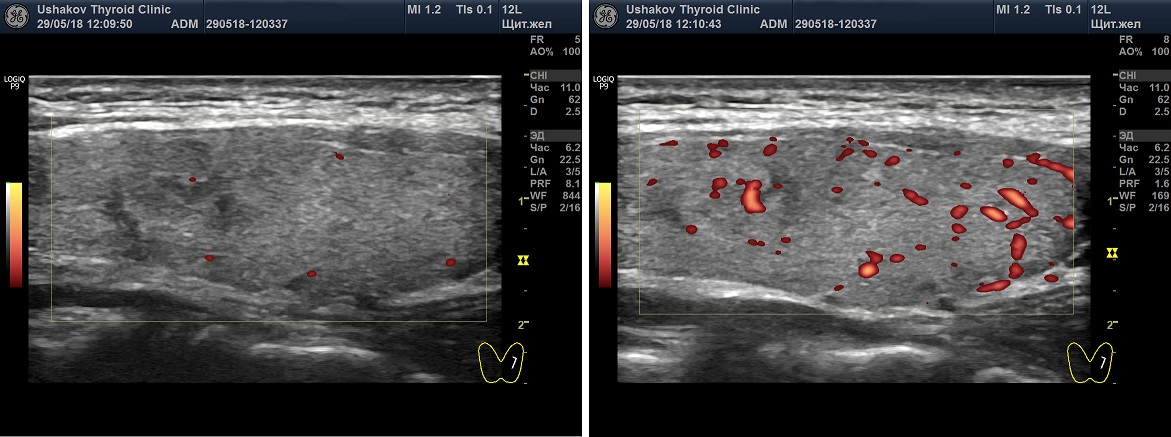

Кровоток в ЩЖ определяется в режиме ЦДК или ЭДК. Многие врачи применяют ЦДК, а не ЭДК, несмотря на меньшее количество искажений при ЭДК. Наша Клиника предлагает всем коллегам выполнять оценку интенсивности кровотока в ЩЖ с помощью ЭДК, а скорость крови в режиме ЦДК, так как ЦДК позволяет цветом различать артерии от вен.

Рисунок 2. Два варианта ультразвукового допплеровского режима ― ЦДК (цветовое допплеровское картирование) и ЭДК (энергетическое допплеровское картирование). Программа УЗ-аппарата показывает сосуды цветом. Красным и синим при ЦДК и алым ― при ЭДК. При ЦДК видны сосуды (артерии и вены), несущие кровь в разных направлениях). При ЭДК не видно направления течения крови, но меньше погрешностей.